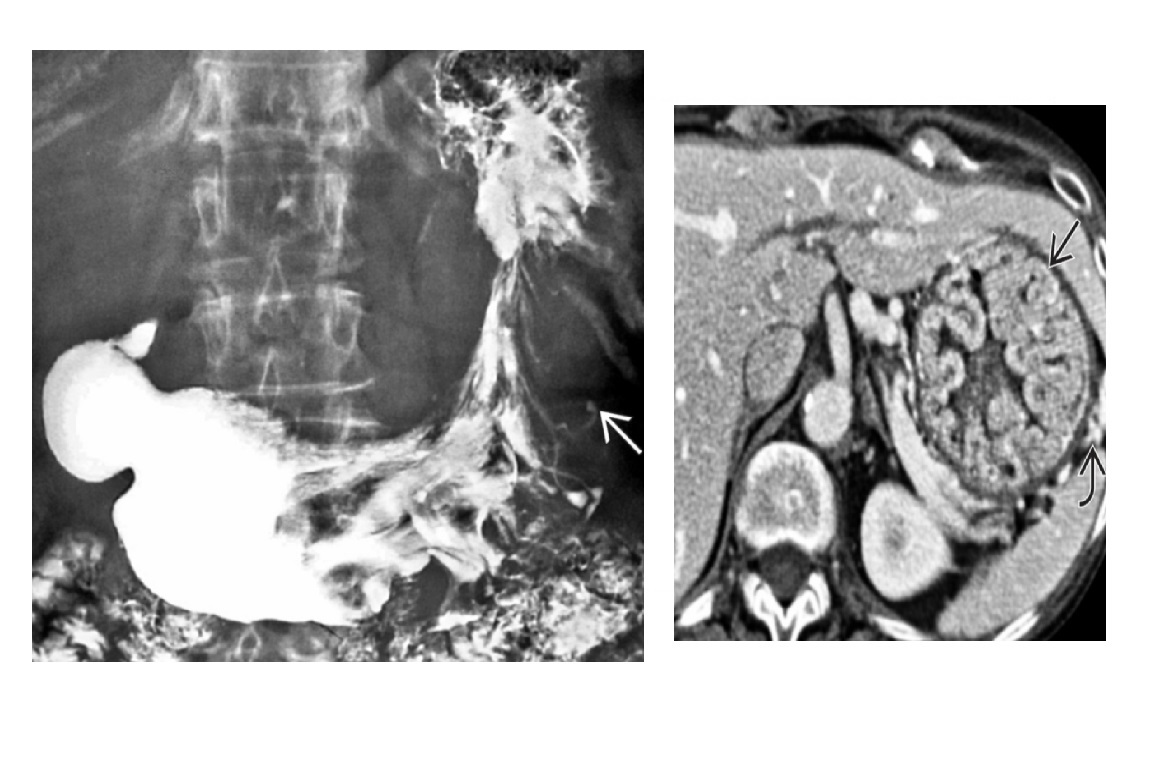

Small bowel spiculated mesenteric mass with calcification. Solidary enhancing ileal lesion

Carcinoid Sunburst desmoplastic reaction in the mesentery Tethering of SB loops 90% arise in terminal ileum/appendix Hyper-vascular liver mets - Carcinoid syndrome **111I- Octreotide scans (1st - highest sensitivity) or 123I-MIBG (for 10% dont take up octreotide) for Dx and staging** Assocaited with MEN 1 or MEN 2a DDX Sclerosing mesenteritis - FAT HALO sign - Mass envelop vessels, but preservation of fat around vessels - usually jejunal small bowel mesentery Gastrointestinal Stromal Tumor (GIST) - Hypervascular tumor, not associated with desmoplastic effect on mesentery Small Bowel Carcinoma - More common in duodenum or jejunum than in ileum - Causes luminal obstruction - Mass and metastases are hypovascular